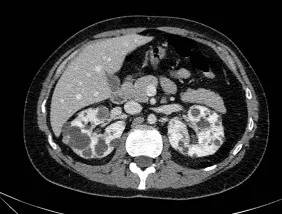

Injúria Renal Aguda (revisão Lancet 2025)

Injúria Renal Aguda (revisão Lancet 2025)